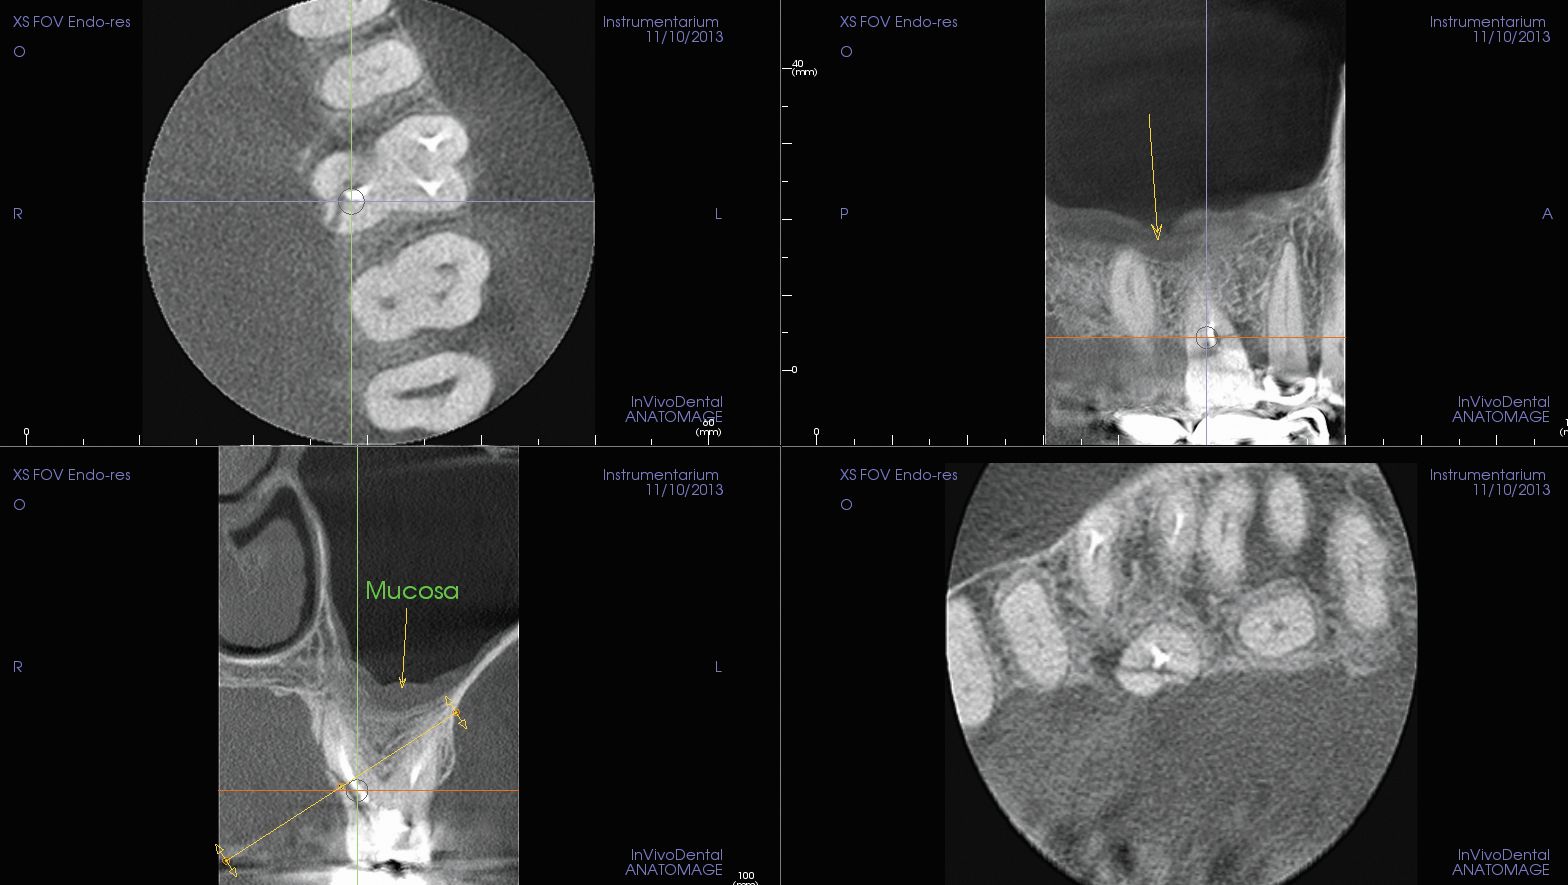

OP300 Maxio features a high-resolution modality to take highly detailed 5x5 cm 3D scans, the ideal support for the most complex endodontic cases. OP300 Maxio helps visualize small anatomical details like fractures and endodontic root fillings.

In addition the Metal Artifact Reduction (MAR) technology reduces the amount of glare produces by metal or opaque objects producing crisp views of the anatomical region of interest.